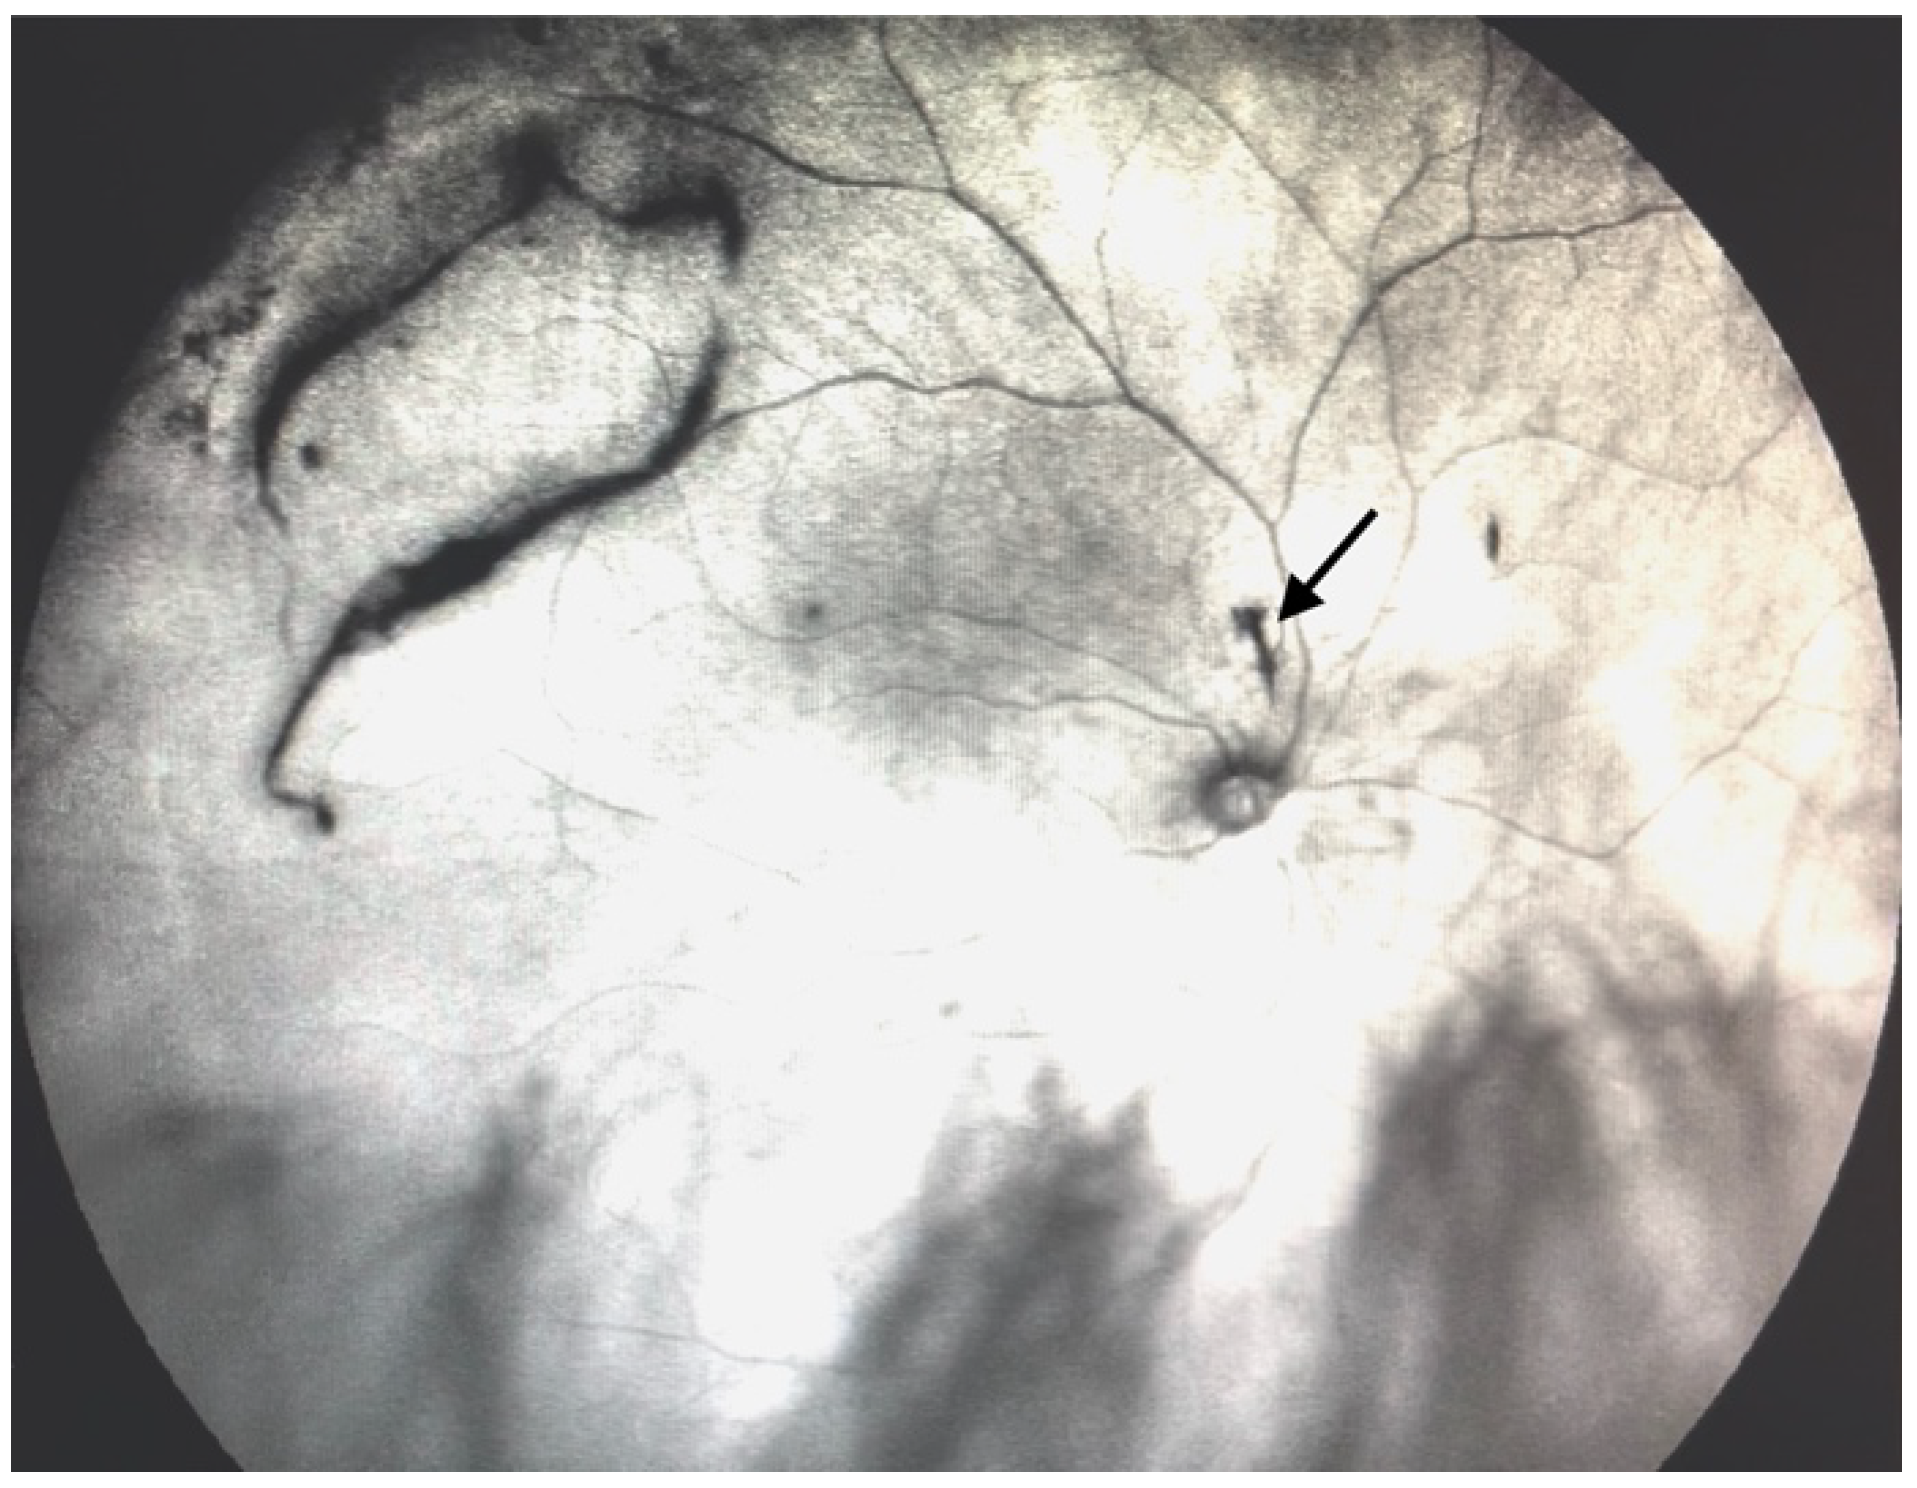

| Grade 3—Dense opacities outside the center of the macula in primary gaze, that cross the center of the macula with eye movement (Figure 5 and Video S5). |